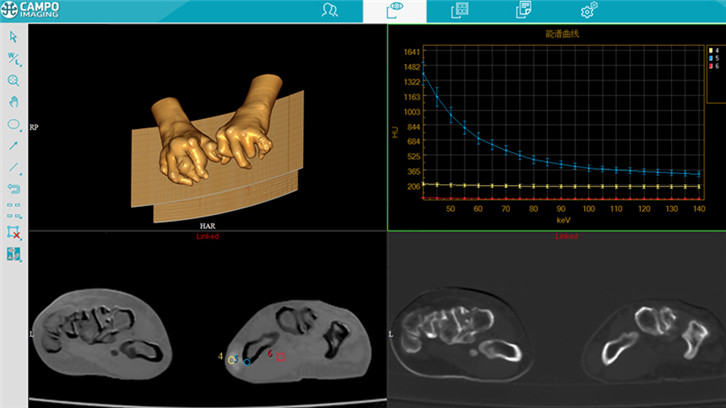

能谱显示

三维图像重建

多平面重建